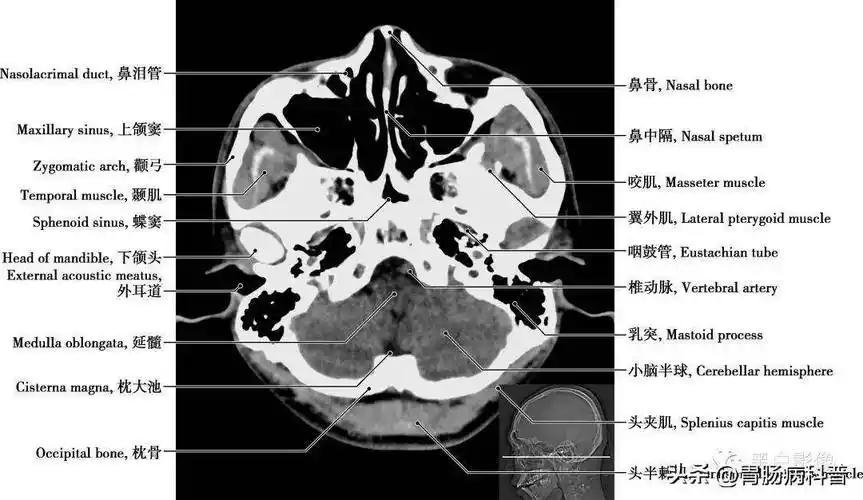

颅脑ct的正常解剖

头颅ct 解剖图谱,人手一份

详细标注版——颅脑ct正常解剖图谱_中央_小脑_纤维